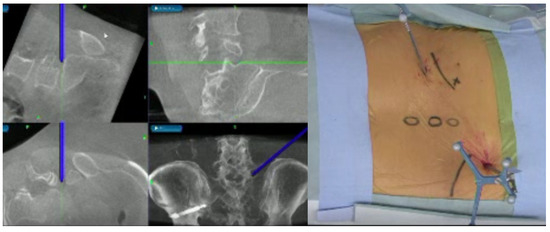

2.2. Image Technique

2.3. CT-MRI Fusion Image